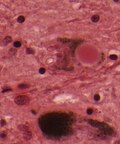

| cytoplasmic vacuolization | | cytoplasmic vacuolization, PrP+ve plaques, Kuru plaques (MV2 variant) | ||

| [http://en.wikipedia.org/wiki/File:SpongiformChangeCJD.jpg] | | [http://en.wikipedia.org/wiki/File:SpongiformChangeCJD.jpg] | ||

*Spongy appearance (cytoplasmic vacuolization<ref>URL: [http://moon.ouhsc.edu/kfung/jty1/opaq/PathQuiz/N0I002-PQ01-M.htm http://moon.ouhsc.edu/kfung/jty1/opaq/PathQuiz/N0I002-PQ01-M.htm]. Accessed on: 19 October 2010.</ref>). | *Spongy appearance (cytoplasmic vacuolization<ref>URL: [http://moon.ouhsc.edu/kfung/jty1/opaq/PathQuiz/N0I002-PQ01-M.htm http://moon.ouhsc.edu/kfung/jty1/opaq/PathQuiz/N0I002-PQ01-M.htm]. Accessed on: 19 October 2010.</ref>). | ||